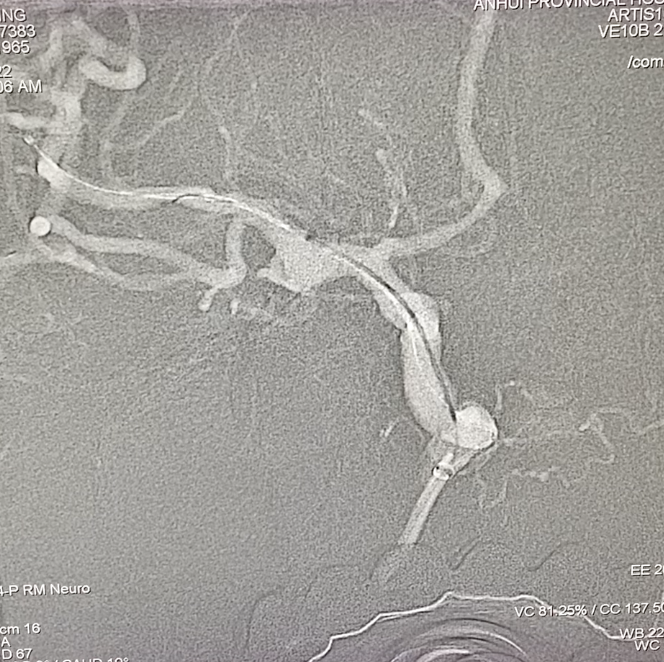

脑血管造影

DSA:右侧大脑中动脉瘤,形态不规则,夹层可能,瘤体可见分支血管,4.5mm×3.2mm,瘤颈5.8mm;远近端载瘤动脉直径分别为2.71mm、2.93mm。